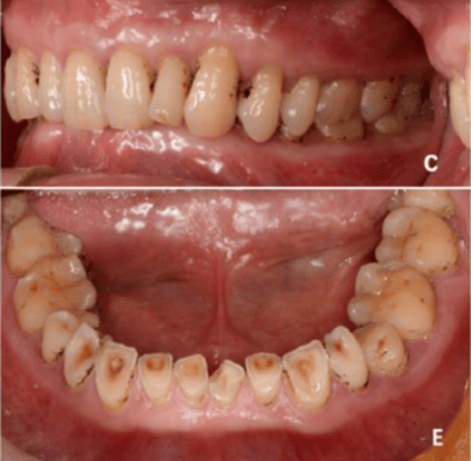

颌重建:适用于重度磨损而引起食物嵌塞的患者。用该方法恢复正常的咬合垂直距离、颌面形态与牙齿外形后,食物嵌塞会随之消失。